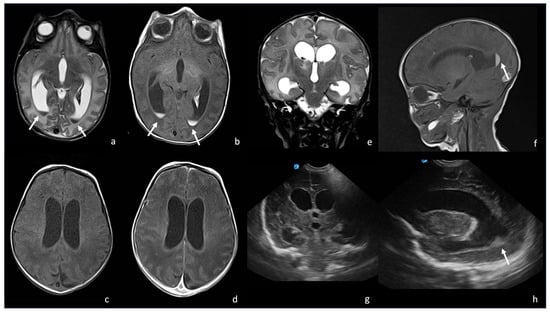

5.1. Choroid Plexitis and Ventriculitis

5.3. Ventriculomegaly and Hydrocephalus

5.4. Effusions and Empyema